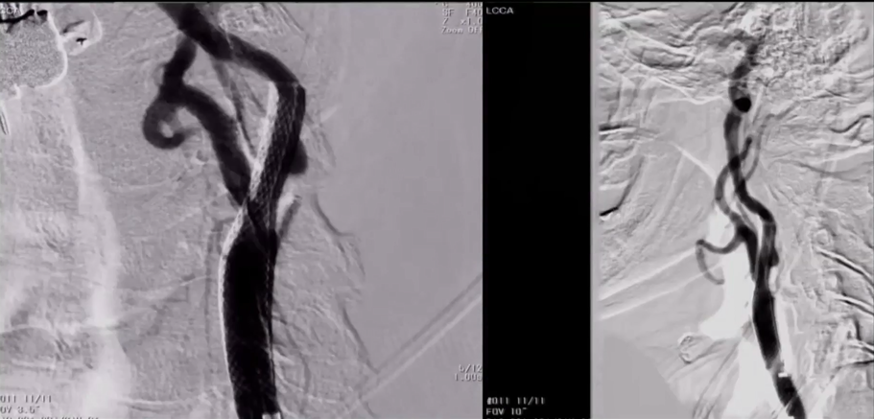

8F Fluxcap®球囊导引导管在5FMPA多功能125cm导管同轴辅助下送至右侧颈总动脉,微导丝送至C4段,沿微导丝送入6mm保护伞至C2段平直段,手推造影显示保护伞打开良好。

沿保护伞导丝送入4.0mm×30mm球囊,充盈球囊导引导管的球囊阻断血流,于狭窄段定位后命名压扩张球囊,泄球囊时在球囊导引导管的体外端予以负压回抽血液,取出一2mm血栓。经Fluxcap®球囊导引导管输送7.0-10.0mm×40mm自膨支架(Protégé RX)至狭窄段确认位置后释放。应用125cm多功能导管回收保护伞,多功能导管体外端予以负压回抽血液,保护伞内有血栓。

造影可见残余狭窄10%左右,颅内各分支血管通畅。